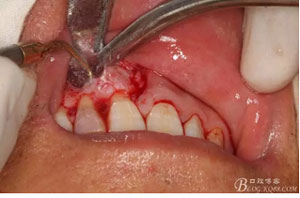

圖4. 唇腭側(cè)局部浸潤麻醉行根尖囊腫摘除術(shù)+根管倒充填。唇側(cè)浸潤要求進針深度比正常麻醉深度要深點,因為還有囊腫的摘除。

圖6.行唇側(cè)角形切口(11近中垂直切口+齦溝內(nèi)水平切口)垂直切口距離前庭溝約1~2mm。這樣可以減輕術(shù)后腫脹。